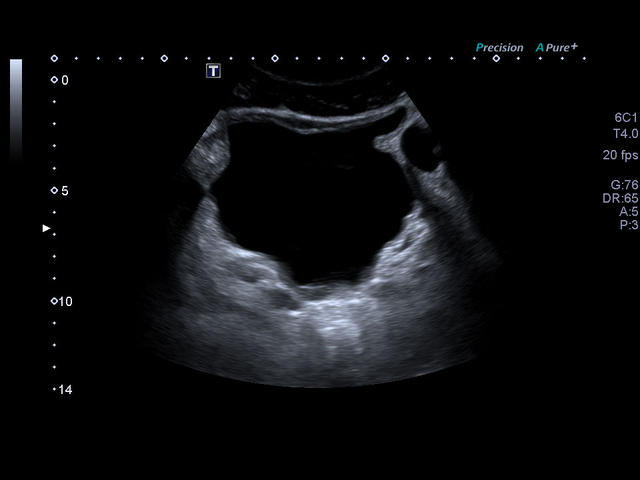

- Абдоминальные исследования

- Превосходное качество изображений и максимальная детализация. Четкое прорисовывание границ и повышенная однородность изображения позволяют без сомнений устанавливать точный диагноз.

- Высокотехнологичное сложное многолучевое сканирование с режимом подавления спекл-шумов в реальном времени - Aplipure plus.

- Одновременная обработка множества смежных ультразвуковых линий Precision Imaging

- Максимальная глубина сканирования: 40 см